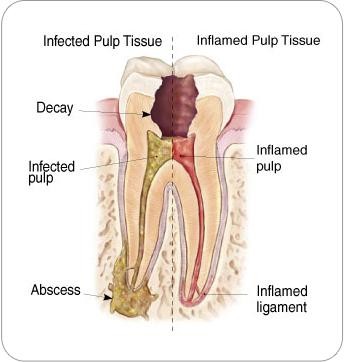

Root canal treatment (RCT) is a dental procedure used to remove

infected or damaged pulp (the soft tissue inside your tooth). The

area is cleaned, disinfected, and sealed to save the natural

tooth.

It is often recommended when the inner pulp becomes inflamed or

infected due to deep decay, cracks, or trauma.

- Persistent tooth pain

- Sensitivity to hot and cold that lingers

- Pain while chewing or biting

- Swollen or tender gums

- Darkening of the tooth

- Pus or abscess around the tooth

If you’re experiencing these symptoms, it may indicate that

the infection has reached the pulp, requiring RCT treatment.